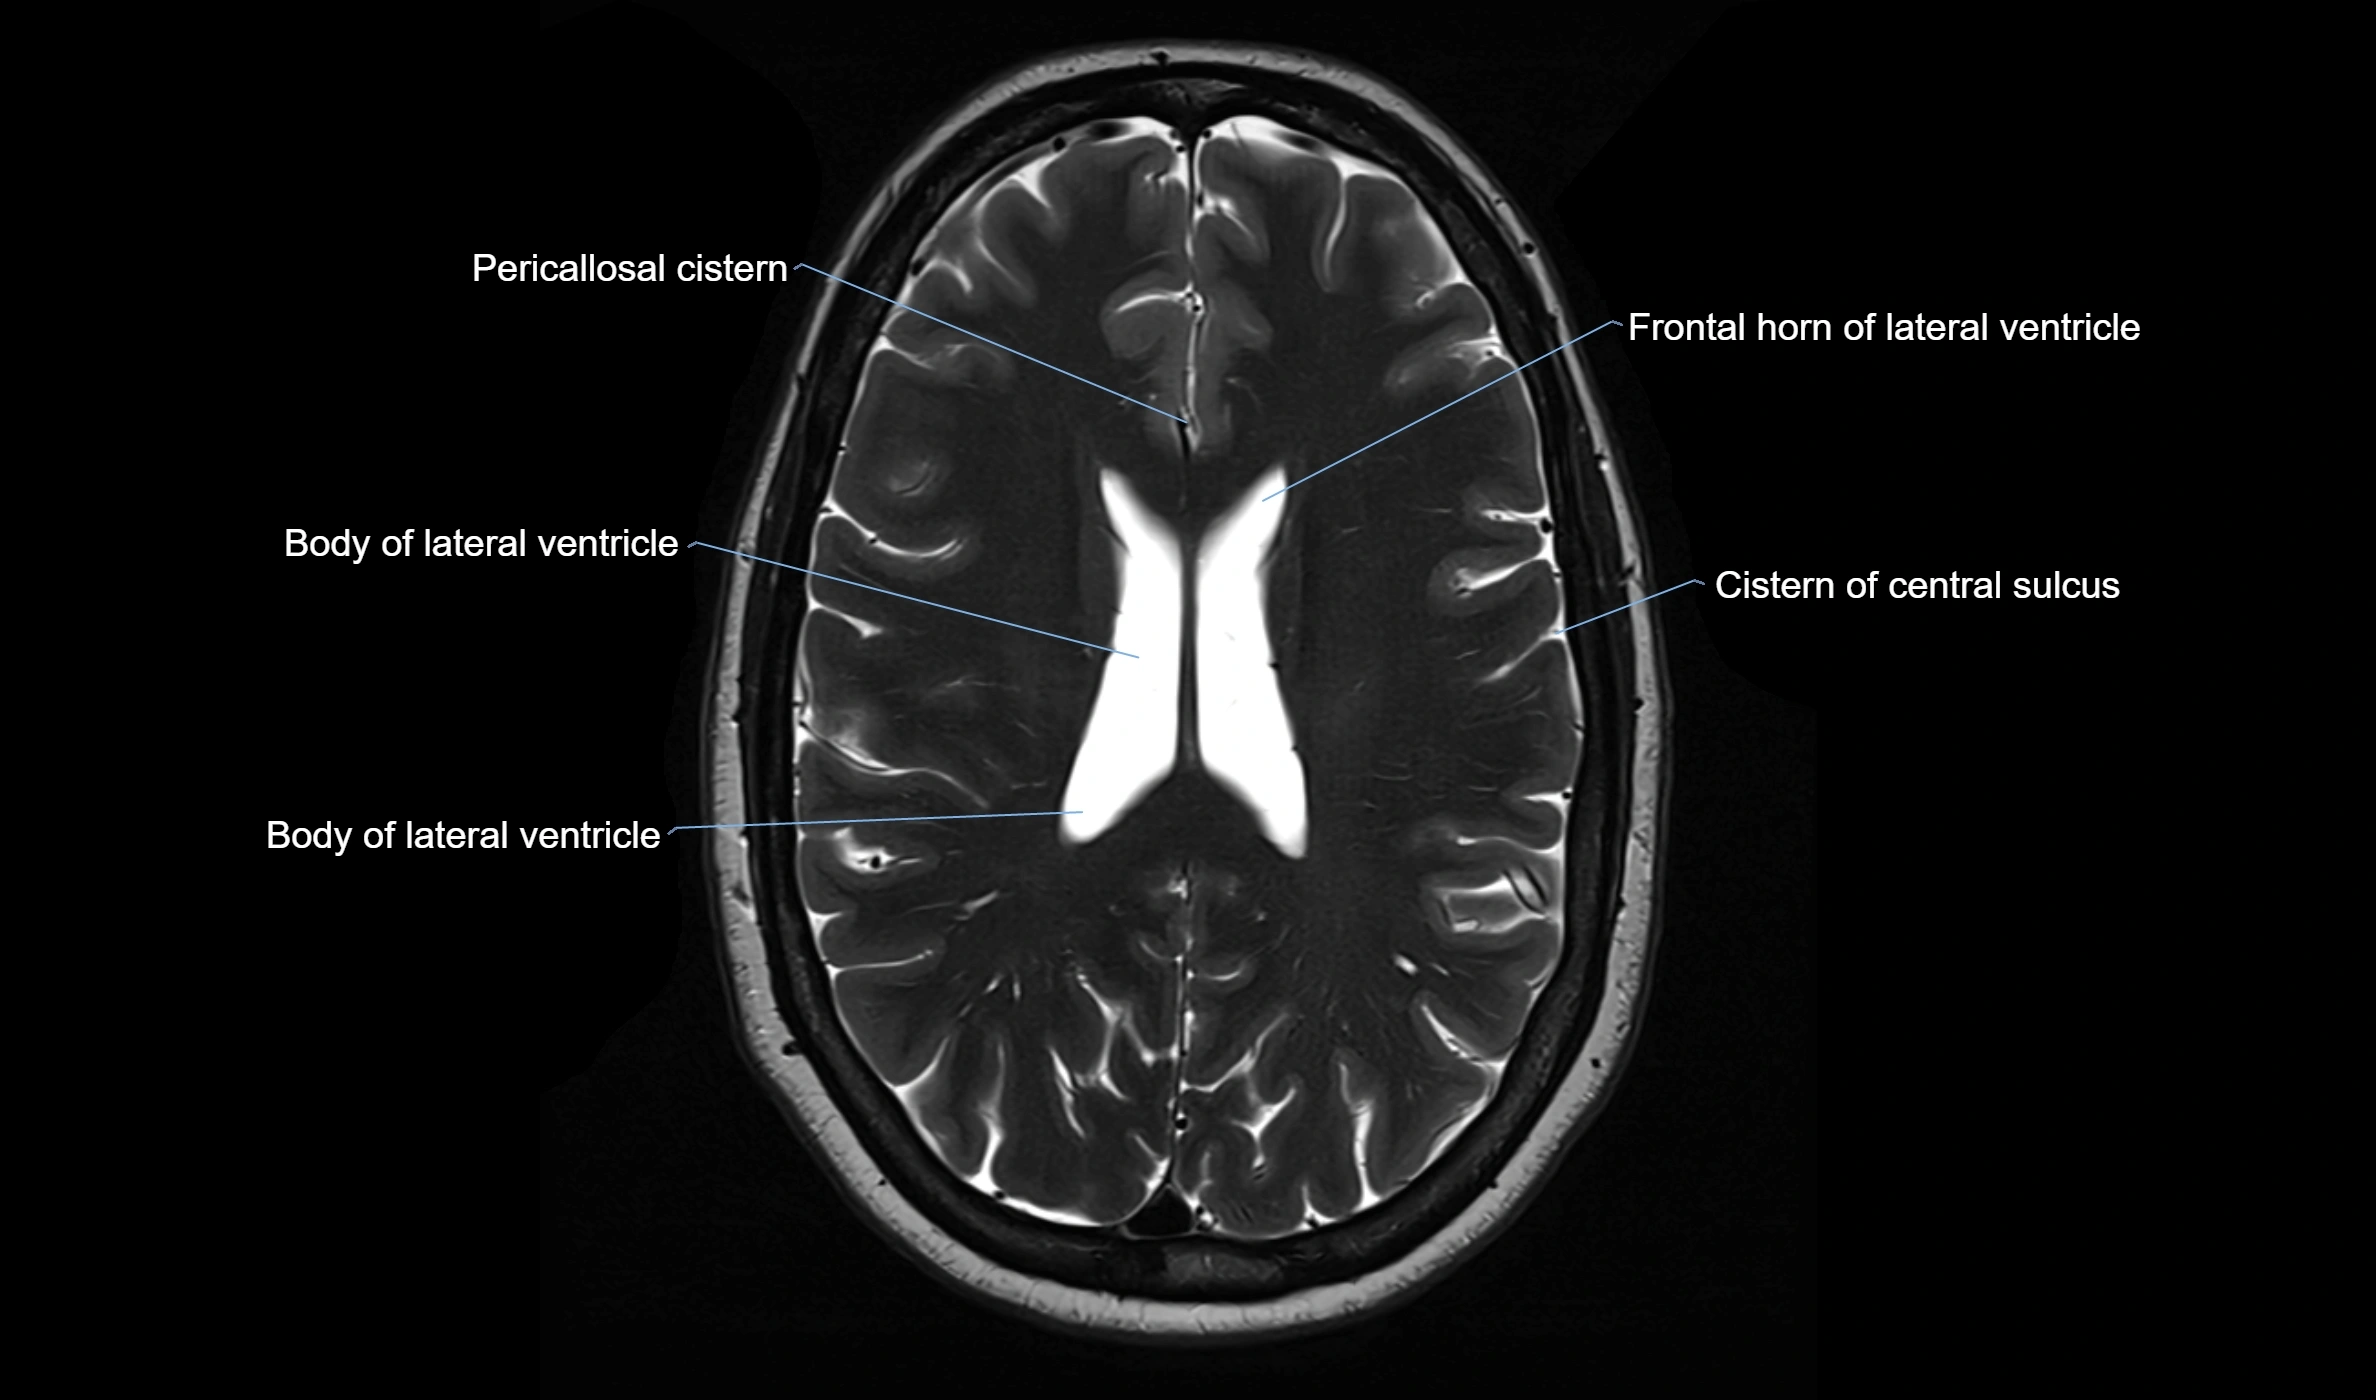

The ambient cistern is a paired, narrow, and elongated subarachnoid space located bilaterally along the lateral aspect of the midbrain. It serves as a conduit between the interpeduncular cistern anteriorly and the quadrigeminal cistern posteriorly. This cistern houses critical neurovascular structures, including parts of the posterior cerebral artery, superior cerebellar artery, trochlear nerve (cranial nerve IV), and the basal vein of Rosenthal. It plays an important role in the circulation of cerebrospinal fluid (CSF) and provides an anatomical corridor for various vessels and nerves passing around the midbrain.

MRI Appearance

• T2-weighted images:

• The cistern is hyperintense (bright) due to the high water content of CSF.

• Encapsulated vessels and nerves are seen as flow voids or hypointense lines within the bright background.